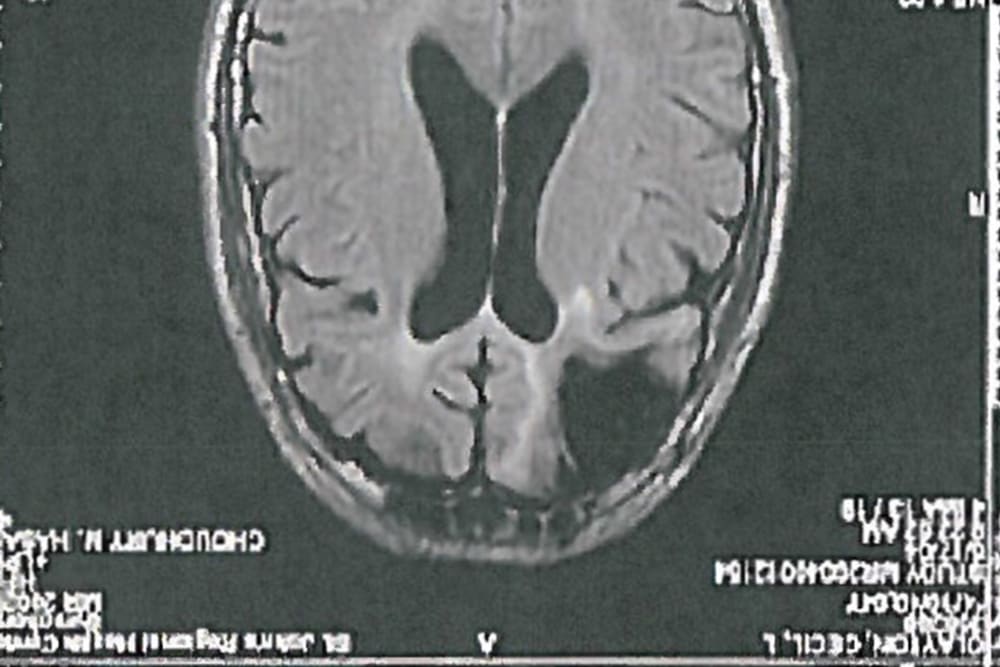

In 1972 — some 24 years before committing the crime for which he was sentenced to death — Clayton was injured in a sawmill accident in which a piece of wood pierced his skull. As a result, doctors removed one-fifth of Clayton’s frontal lobe, the part of the brain that controls decision-making, mood, and impulse-control. Thereafter, Clayton “broke up with his wife, began drinking alcohol and became impatient, unable to work and more prone to violent outbursts,” one of his brothers told The Atlantic. His IQ dropped, and in 1983, Clayton was diagnosed with chronic brain syndrome, a condition said to decrease mental function.

“Mr. Clayton’s IQ, since his accident and subsequent deterioration, now falls within the range required for intellectual disability,” the defense wrote in its appeal to the high court. “And there is substantial evidence of adaptive deficits; Mr. Clayton, even in prison, cannot without assistance order canteen items or navigate the telephone system.”